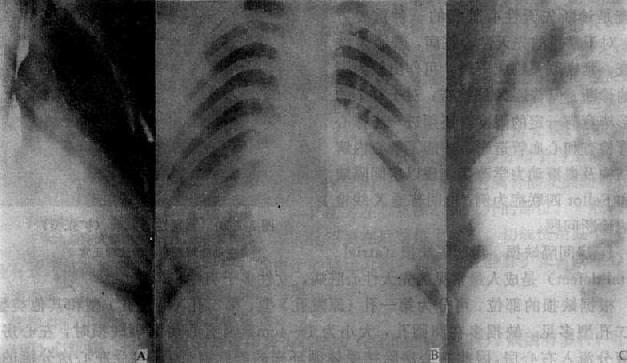

图3-2-21 房间隔缺损

右前斜位:右心室增大,肺动脉段突出,心前间隙变窄,无左心房增大后前位:心增大,呈二尖瓣型,右心房及右心室增大,肺动脉段突出,肺纹理增强左前斜位:右心房及右心室增大,左心室被增大的右心室推向后